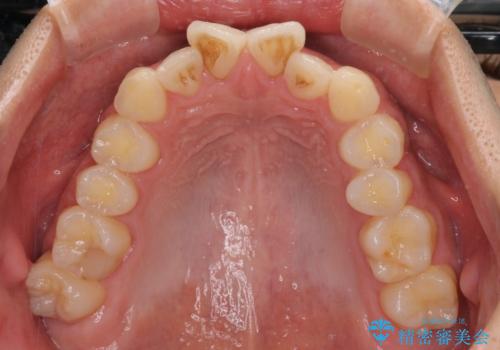

捻れて飛び出した前歯 インビザラインで整った前歯に

- 上下前歯のデコボコと、それに伴う出っ歯を気にして来院された患者様です。

インビザラインによる上下歯列の側方拡大と後方移動、IPR(歯と歯の間を削る)にるスペースの獲得により歯列を整えることとしました。